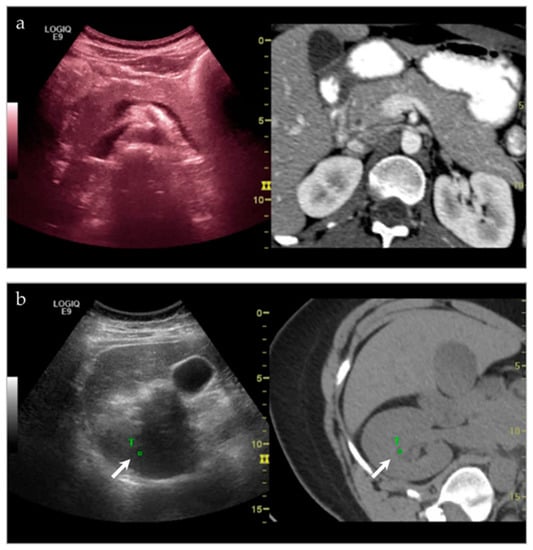

| NA **/F | Right psoas muscle | US-CT fusion | Abscess | Infection |

| NA/F | Right parasternal region | US-CT | Metastatic disease, lung adenocarcinoma | Neoplastic, malignant |

| NA/NA | Left paraspinal region | US-CT | Metastatic disease, unknown carcinoma | Neoplastic, malignant |

| 17/M | Acromioclavicular joint | US-MRI | Metastatic disease, nasopharyngeal carcinoma | Neoplastic, malignant |

| 63/F | Left posterior iliac bone | US-PET | Metastatic disease, breast carcinoma | Neoplastic, malignant |

| 51/F | Left inferior pubic ramus | US-CT | Metastatic disease, breast carcinoma | Neoplastic, malignant |

| 45/M | Right acromion | US-MRI | Epithelioid hemangioma | Neoplastic, benign |

| 54/F | Left midfoot | US-MRI | Metastatic disease, melanoma | Neoplastic, malignant |

| 24/M | Right inferior pubic ramus | US-CT | Ewing sarcoma | Neoplastic, malignant |

| 93/M | Right femur | US-MRI | Metastatic disease, papillary thyroid carcinoma | Neoplastic, malignant |

| 51/M | Left parasymphyseal pubis | US-CT | Fibrous dysplasia | Metabolic |

| 54/F | Right acetabulum | US-CT | Metastatic disease, endometrial carcinoma | Neoplastic, malignant |

| 18/F | Left posterior knee | US-MRI | Parosteal osteosarcoma, with a chondroblastic component | Neoplastic, malignant |

| 60/F | Right anterior leg | US-MRI | Metastatic disease, endometrial carcinoma | Neoplastic, malignant |

| 53/M | Right thigh | US-CT | Necrotic muscle | ???? *** |